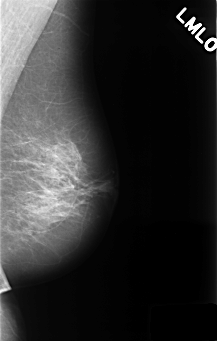

C_0398_1.LEFT_MLO

LEFT_MLO LINES 4424 PIXELS_PER_LINE 2816 BITS_PER_PIXEL 12 RESOLUTION 50 NON_OVERLAY